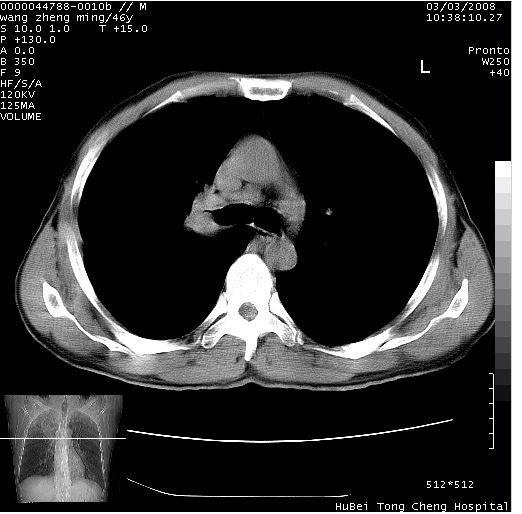

以下是引用卜一在2008-3-22 1:37:00的发言:[br]右肺实质性肿块,边缘不整,明显见毛刺征 分叶征及胸膜凹陷征,右上叶支气管明显变窄,远端散在的片状 斑片状实变影。另:左肺门较大肿块,支气管受累 变窄,远侧见阻塞性肺炎。纵隔内见肿大淋巴结。多考虑:右肺周围性肺癌伴左肺门 纵隔淋巴结转移!